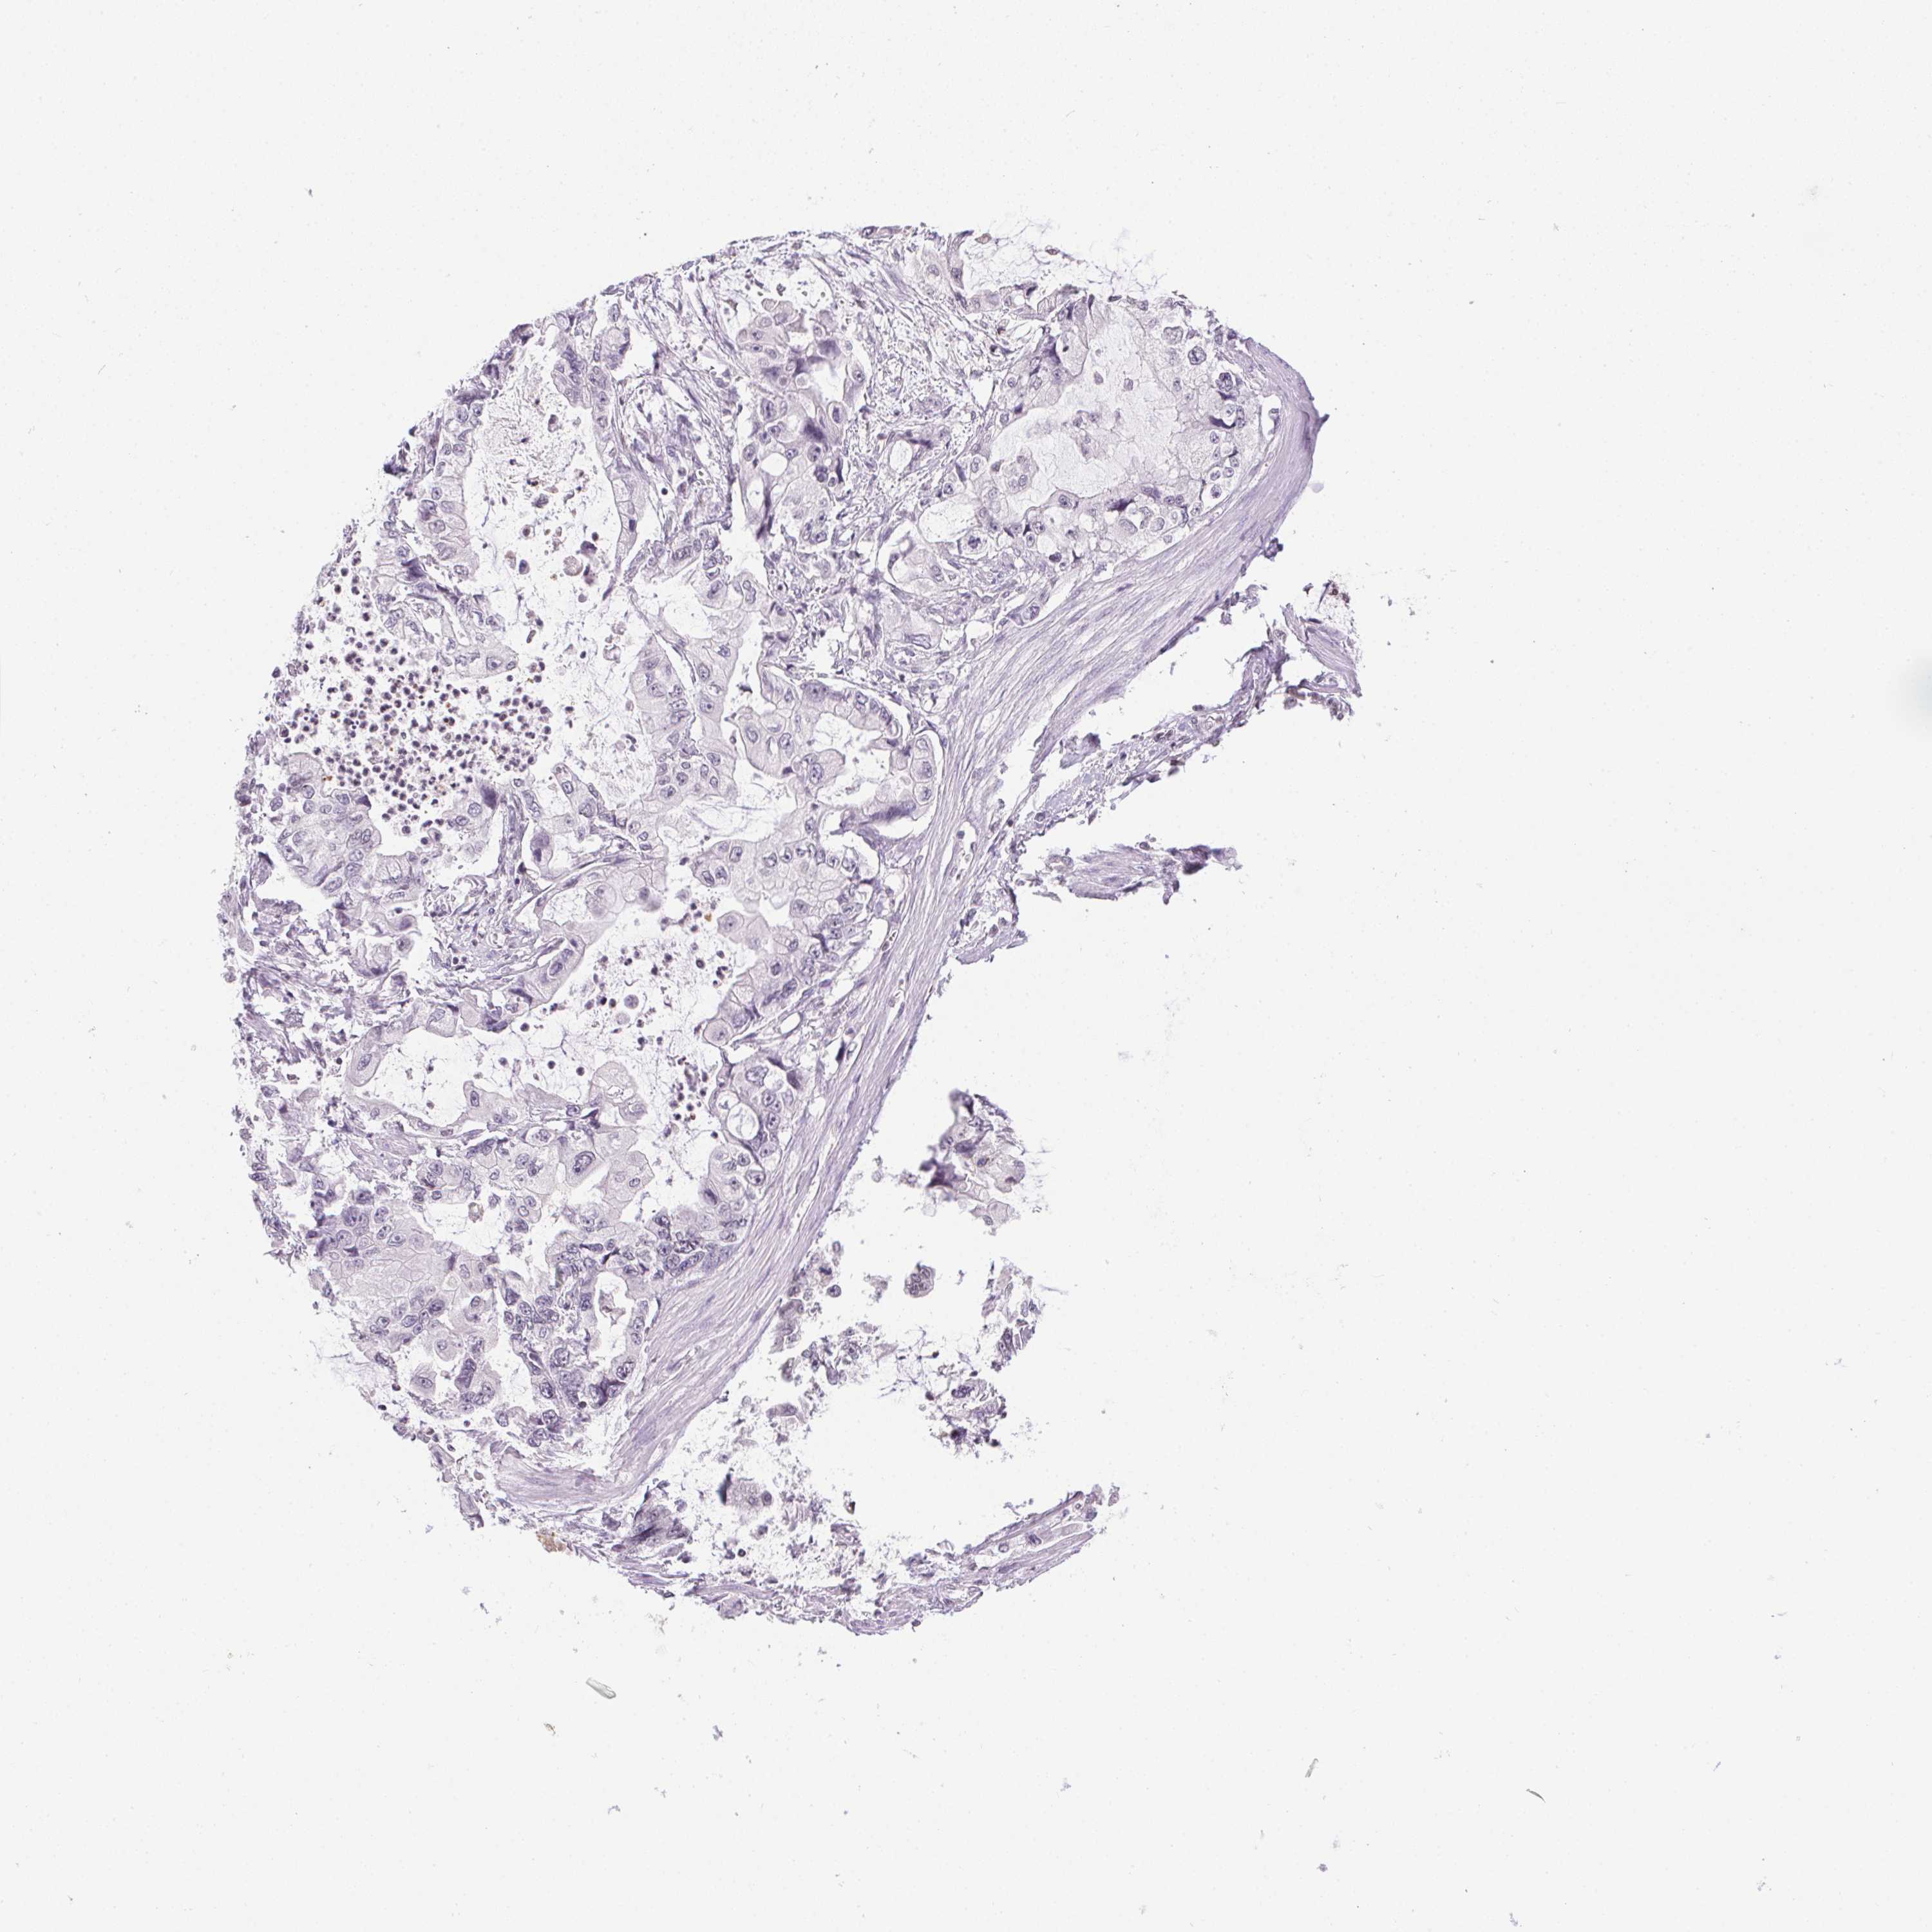

STOMACH CANCER - Protein expressioni

A mouse-over function shows sample information and annotation data. Click on an image to view it in a full screen mode. Samples can be filtered based on level of antibody staining by selecting one or several of the following categories: high, medium, low and not detected. The assay and annotation is described here.

Note that samples used for immunohistochemistry by the Human Protein Atlas do not correspond to samples in the TCGA dataset.

Antibody stainingi

Antibody staining in the annotated cell types in the current human tissue is reported as not detected, low, medium, or high, based on conventional immunohistochemistry profiling in selected tissues. This score is based on the combination of the staining intensity and fraction of stained cells.

Each image is clickable and will lead to virtual microscopy that enables deeper exploration of all samples and also displays staining intensity scores, fraction scores and subcellular localization as well as patient and tissue information for each sample.

Antibody HPA042416

Staining

High

Medium

Low

Not detected

Intensity

Strong

Moderate

Weak

Negative

Quantity

>75%

75%-25%

<25%

None

Location

Nuclear

Cytoplasmic/membranous

Cytoplasmic/membranous,nuclear

Adenocarcinoma, NOS